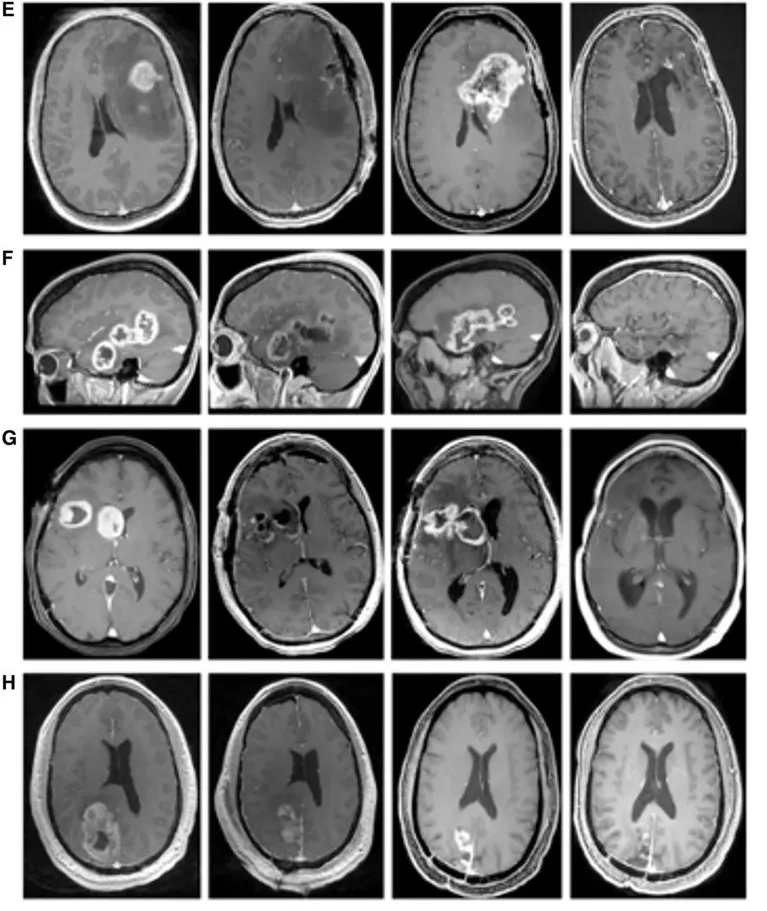

《Cureus》曾报道一个“WT1-DC疫苗治疗晚期肺癌,获得显著疗效的案例”:该患者是一位69岁男性,确诊为右肺中叶IV期鳞状细胞癌,因无法耐受手术及放疗,遂入组接受WT1树突状细胞疫苗(WT1-DC)+化疗(紫杉醇+卡铂AUC6)联合治疗方案。

治疗效果呈现明确获益:CT检查显示,治疗前患者右下肺原发病灶伴胸腔积液,治疗114天后原发灶几乎消失;治疗第213天时虽出现复发迹象,但338天后复查可见复发灶缩小(详见下图)。

▲图源“Cureus”,版权归作者所有,如无意中侵犯了知识产权,请联系我们删除